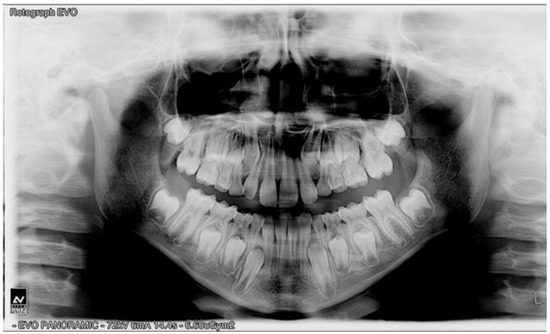

3.1. Clinical Outcomes